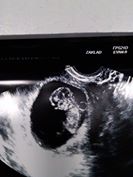

Tak hlásím, že kontrola dopadla výborně, máme okolo 3 cm srdíčko tlouklo a je prý pěkně živý, vrtělo se a mávalo ručičkama i nožičkama

Pájo gratuluju ke kontrole, máš krásnou fotečku, úplně mě to dojalo, je to super.